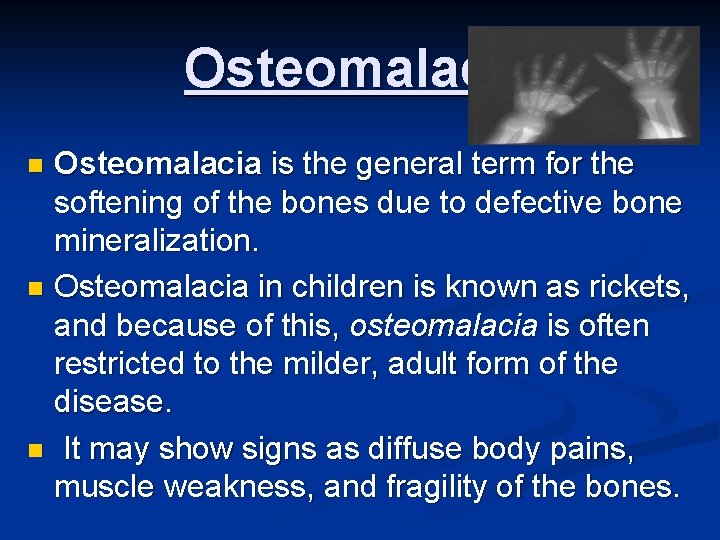

Osteomalacia is the general term for the softening of the bones due to defective bone mineralization. n Osteomalacia in children is known as rickets, and because of this, osteomalacia is often restricted to the milder, adult form of the disease. n It may show signs as diffuse body pains, muscle weakness, and fragility of the bones. n

General characteristics n n Osteomalacia is derived from Greek: osteo refers to bone, and malacia means softness. Osteomalacia in the adult is most commonly found in confined, dark-skinned, or diet-disbalanced subjects. Many of the effects of the disease overlap with the more common osteoporosis, but the two diseases are significantly different. Osteomalacia is specifically a defect in mineralization of the protein framework known as osteoid. This defective mineralization is mainly caused by lack in vitamin D.